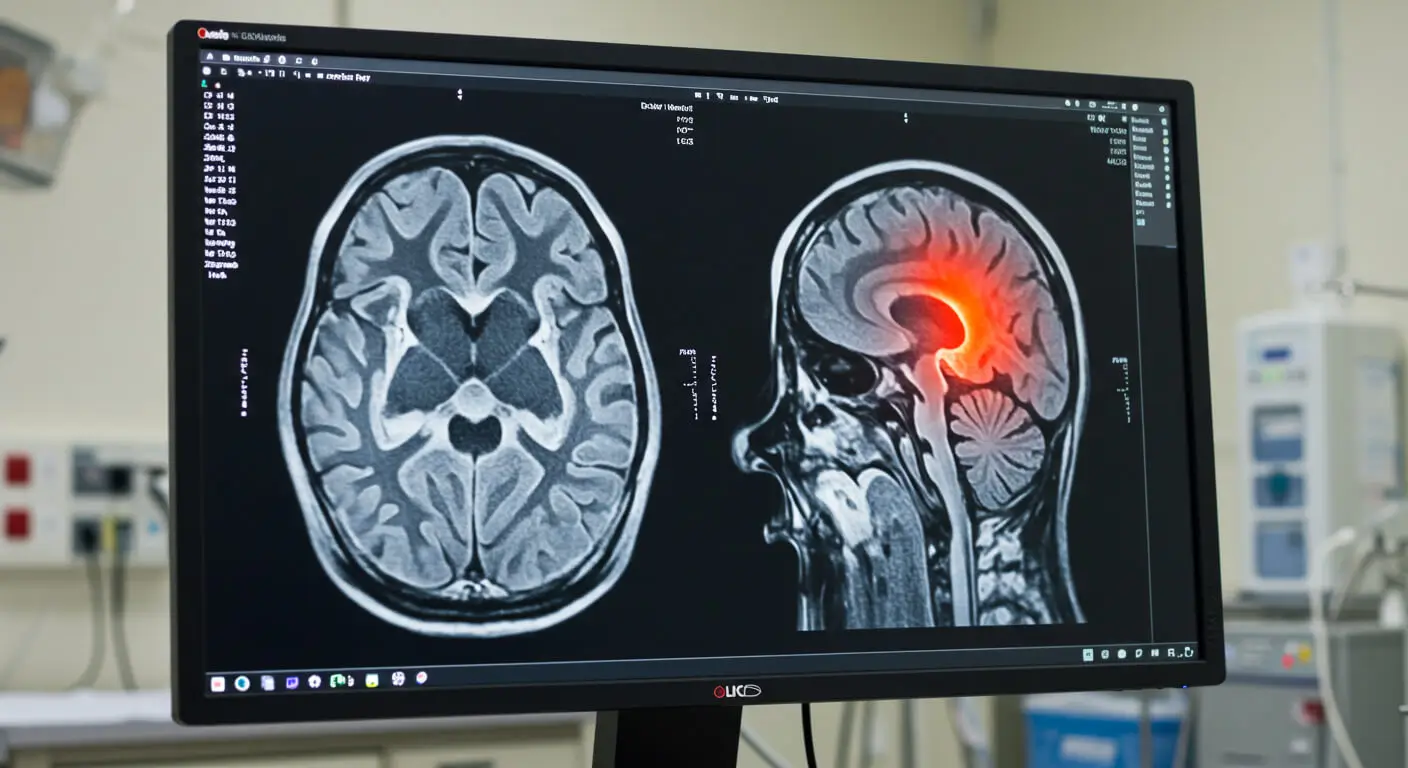

Have you or a loved one sustained a traumatic brain injury or severe head injury? The recovery can be a long and excruciating process. Traumatic Brain Injuries (TBI) can have long-lasting physical and emotional effects that impact every area of life. The treatment expense, from initial assistance to post-hospitalization rehabilitation, can be staggering, especially for those without coverage.

Brain and head injuries involve damage to the skull, brain, or surrounding tissues. They can range from mild to severe and impact a person’s physical and emotional health and overall behavior.

Some common types of brain injuries include traumatic brain injury (TBI), concussions, and other injuries.

1. Traumatic Brain Injury: A TBI generally occurs when the patient suffers a blow to the head that might affect the functioning of brain cells.

2. Concussion: A concussion is a mild TBI caused by a blow or jolt that moves the brain inside the skull, temporarily affecting cognitive function.

3.  Contusion: A contusion (also called bruising of the brain) occurs when an impact causes the brain to swell due to bleeding from the organ.

Head injuries, if severe or left untreated, may have long-term effects on the functioning of the brain and the general health of a victim. Even slight traumas, such as concussions, can lead to memory loss, difficulties in concentrating, or confusion.

Serious injuries can result in long-term disability, such as permanent cognitive impairment, problems with motor function, or behavioral changes. Falls, road vehicle accidents, sports injuries, and even medical malpractice are some of the common causes of brain and head injuries. They may happen both at home and in the workplace.